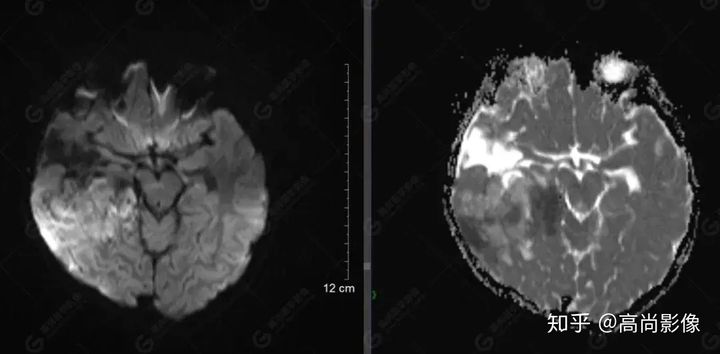

右側(cè)顳葉腫瘤切除術(shù)后(具體不詳):右側(cè)顳部骨質(zhì)不連續(xù)呈術(shù)后改變,右側(cè)顳葉術(shù)區(qū)見片狀長T1長T2信號(hào)影,F(xiàn)LAIR呈低信號(hào);術(shù)區(qū)后方右側(cè)顳枕葉見一巨大占位性病變影,邊界欠清,大小約6.2×5.8×4.3cm(前后×左右×上下),信號(hào)不均勻,T1WI呈等稍低信號(hào)間雜少許高信號(hào),T2WI呈高稍低混雜信號(hào),DWI示部分病灶彌散受限,相應(yīng)ADC圖減低,磁敏感序列見部分呈極低信號(hào),增強(qiáng)掃描可見明顯不均勻強(qiáng)化,鄰近硬腦膜及小腦幕增厚并明顯強(qiáng)化;另延髓右前方及右側(cè)橋小腦角區(qū)見一不規(guī)則形異常信號(hào)影,大小約3.2×1.3×3.7cm(左右×前后×上下),呈長T1稍長T2信號(hào),F(xiàn)LAIR呈等信號(hào),DWI未見受限,增強(qiáng)后明顯均勻強(qiáng)化,鄰近腦膜明顯強(qiáng)化。鄰近腦實(shí)質(zhì)及右側(cè)顳角明顯受壓;左側(cè)大腦半球未見局灶性信號(hào)異常,中線結(jié)構(gòu)稍左移。